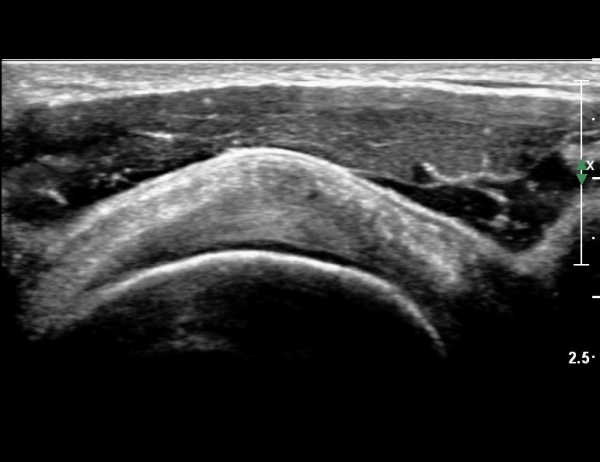

ÀÌµÎ¹Ú±Ù°Ç È¾´Ü¸é°Ë»ç¿¡¼­ °Ç ÁÖÀ§ ¼ö¾×Àú·ù µî ƯÀÌ ¼Ò°ßÀ» º¸ÀÌÁö ¾Ê¾Ò´Ù(»çÁø 1, 2)